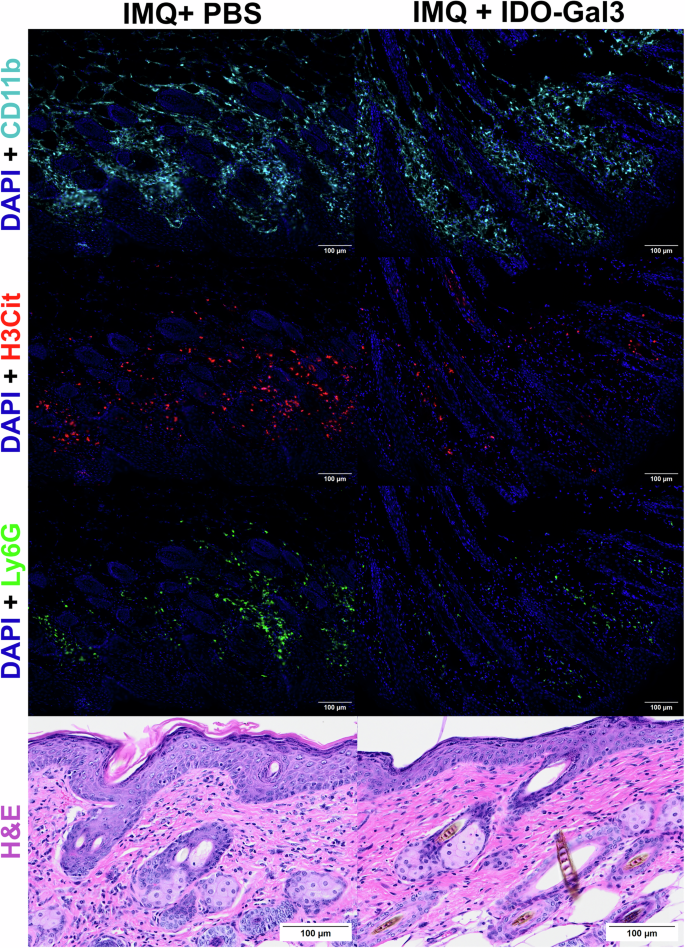

Further histological observations at day 14 via immunofluorescence and H&E staining were consistent with reduced immune cell infiltration and inflammatory markers after IDO-Gal3 treatment. Specifically, in IDO-Gal3 treated skin, CD11b+ macrophages, Ly-6G+ neutrophils, and the neutrophil NETosis marker, citrullinated histone H3 (H3Cit), appeared to be trending lower (Fig. 2), as did total infiltrating cell populations via H&E stain. Quantitative assessment by image analysis, however, did not yield p-values meeting our criteria for significance (Supplement Fig. 3), limiting interpretation of these images to qualitative descriptions.

Representative immunofluorescence staining and light microscopy images of day 14 psoriatic skin after treatment with PBS (left) or IDO-Gal3 (right). IDO-Gal3 treatment resulted in the appearance of reductions in intensity of myeloid CD11b+ staining (teal), NETosis marker H3Cit (citrullinated histone H3 regions; red), and infiltrating Ly-6G+ neutrophil number (green), with cell nuclei stained with DAPI (blue). Infiltrating cell number observed via H&E stain appeared reduced with IDO-Gal3 treatment. 20X magnification, scale bars 100 µm.